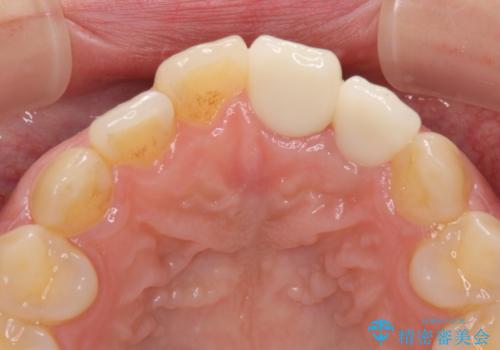

既にクラウンが装着されていた歯は歯根の先端に病変が認められたため、根管治療を行うこととしました。

仮歯装着の時点で自然な見た目となり、オールセラミッククラウンを装着した際には、まるで自分の歯のようと喜んでくださいました。

長年変色を気にしており、もっと早くに治療を行えば良かったとおっしゃっていました。